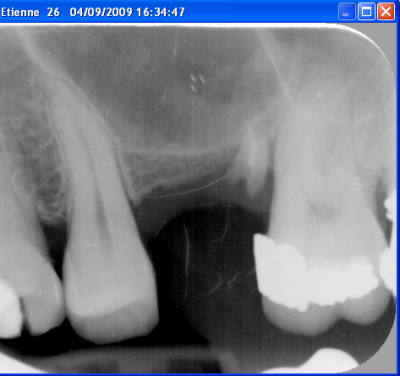

Le cas date de 2010, le sinus est traité par élévation crestale + mise en place de 2 mb de PRF dans le "trou" avant de combler au RTR et en dernier os récupéré du forage pour espérer qu'il reste contre l'implant.

J'ai pas pu enlever le prénom mais vous avez les dates dans l'ordre

Qu'est-il arrivé à la 23? Elle présentait un soin mal adapté en 2009, puis a été couronnée en 2010, et aujourd'hui, plus rien, disparue...

comme tu le vois sur la première radio du premier post, elle va bien avec un composite distal